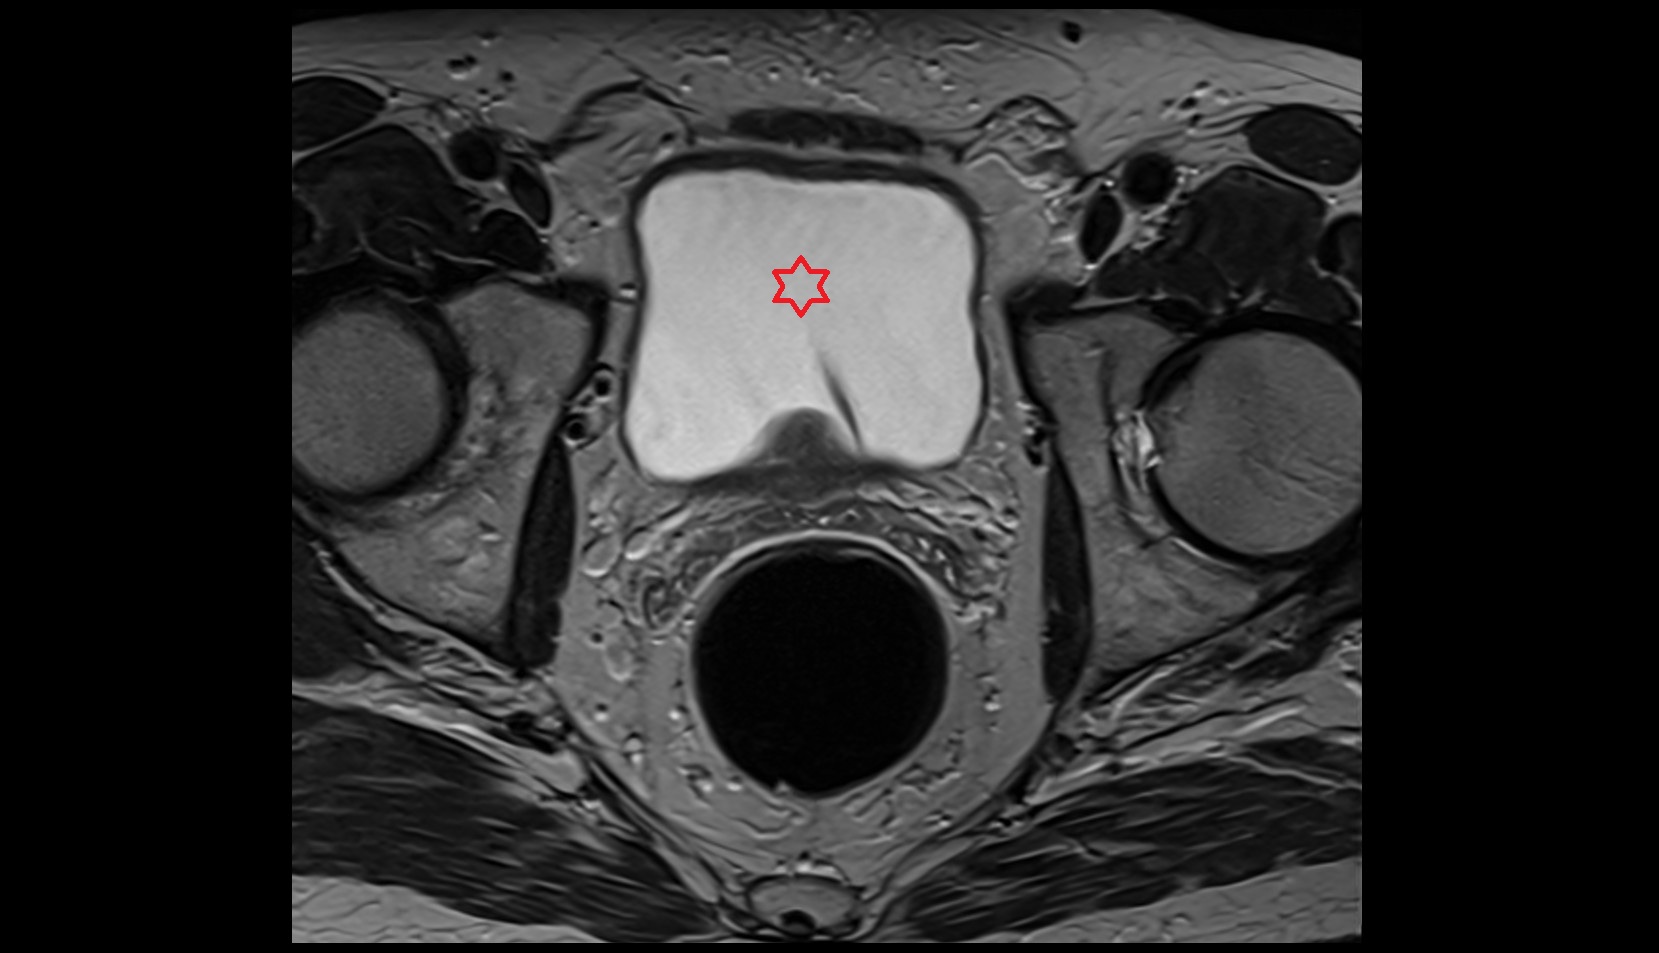

- Urinary bladder

- Uterus

- Pubic symphysis

- Rectum